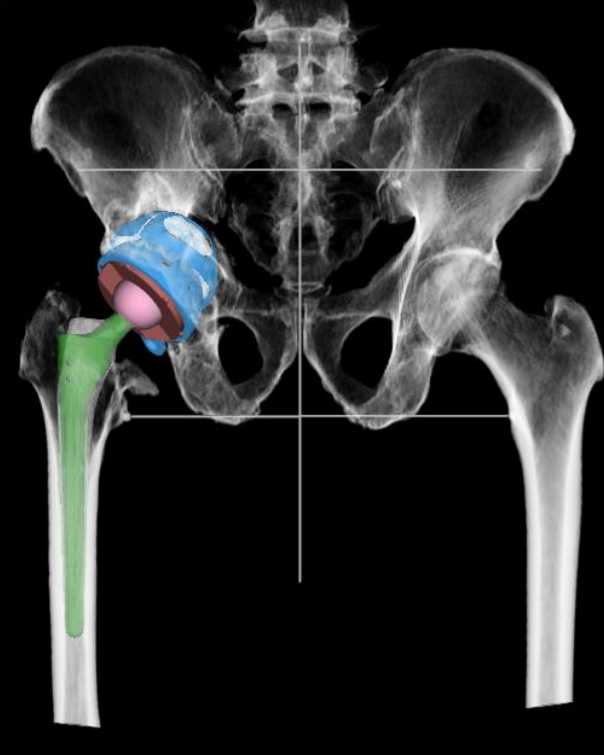

近日,由浙江大学医学院附属第一医院雷鹏飞教授团队顺利完成浙江首台VTS可视化智能辅助系统配合爱康HDR翻修系统+个性化定制3D打印多孔金属补块的复杂翻修手术。术中使用72毫米直径髋臼杯,结合3D打印个性化定制翻修补块,在VTS系统辅助下精准放置于规划位置,成功修复髋臼巨大骨缺损。

术后雷鹏飞教授表示,VTS系统与HDR系统首次搭档获得了良好的术后效果,VTS系统的引入让复杂手术简单化,术前规划让手术更安全,术中辅助指引让手术更精准。HDR定制外杯采用非组配设计,假体整体为EBM技术3D打印多孔结构,具有较高的粗糙度和摩擦系数。由于无需设计与内衬的连接结构,因此螺钉孔的布置更加灵活,为俗称的“满天星”设计,便于在残留的宿主骨上进行螺钉固定,实现牢靠的初始稳定性。

Visual Treatment Solution™(简称:VTS)是凭借医工交互进行术前规划与可视化实时监控的解决方案,旨在提升全髋关节置换术的手术性能和临床疗效。该系统将3D打印数字化制造技术与可视化智能辅助技术相结合,适应髋关节置换术中复杂的工作环境,从术前CT数据处理、3D手术规划,到术中的实时可视化追踪及髋臼假体植入等全流程进行辅助。